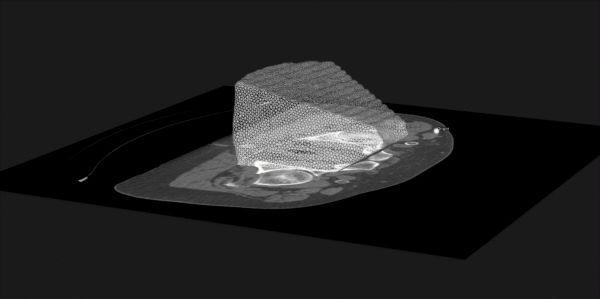

- The Use of Hybrid Imaging in Radiotherapy Treatment Planning